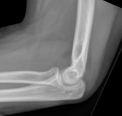

Findings may be quite subtle and the only clue may be the fat pad sign (triangular radiolucent shadows anterior and posterior to the distal humerus on lateral X-ray, indicating haemarthrosis and displacement of intra-articular fat pad - often associated with intra-articular skeletal injury).

Image of elbow fat pad sign (Hellerhoff (own work), via Wikimedia Commons):

Elbow fat pad sign